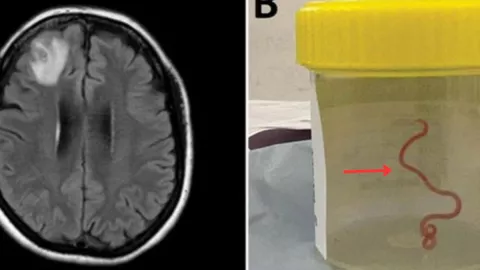

Una resonancia magnética que le fue practicada reveló algo inusual en el lóbulo frontal derecho de su cerebro así que decidieron someterla a una operación quirúrgica cerebral.

Fue entonces que los médicos encontraron el gusano vivo en su cerebro y lo extrajeron para después mandarlo a examinar y saber qué tipo de parásito era.

Expertos en parasitología encontraron que se trata de un Ophidascaris robertsi, un parásito que suele habitar en las pitones alfombra que se encuentran en el sureste de Nueva Gales del Sur.